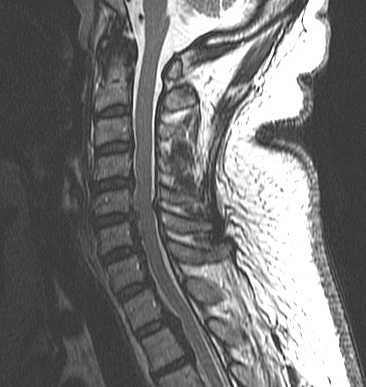

МРТ позвоночника. Сагиттальная Т2-взвешенная МРТ шейного отдела позвоночника. Стеноз позвоночного канала обызвествленной задней продольной связкой.

КТ шейного отдела позвоночника. Реконструкция в сагиттальную плоскость. Оссификация задней продольной связки.